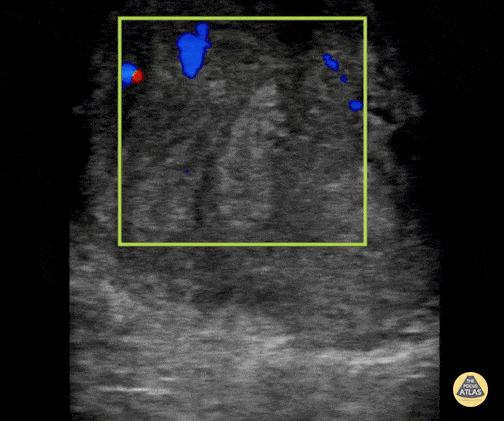

16 year old male with right testicular pain and swelling presented to the emergency department, a POCUS was done showing increased flow in the left testicle along with surrounding edema. This ultrasound clip demonstrates increased flow to the left testicle. This can be better appreciated when compared in a side by side view to the normal testicle. Diagnosis of orchitis was made and confirmed with radiology performed ultrasound. Contributor: Zach Boivin, MD, @ZachBoivinMD